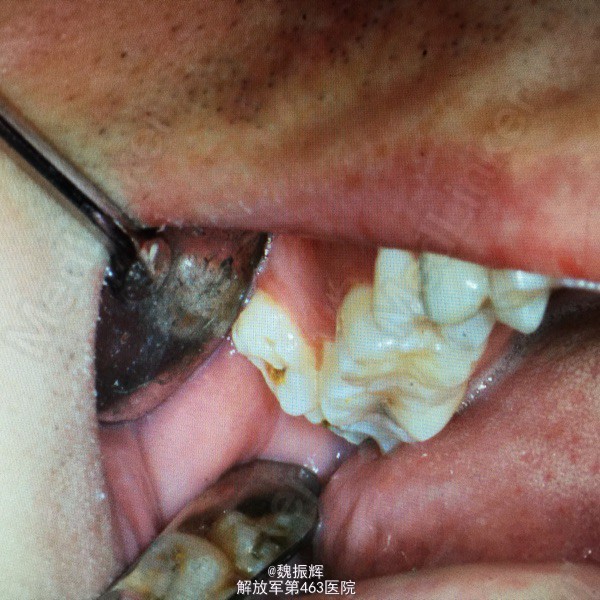

第四磨牙

患者男性,32岁,右上后牙经常咬颊来院就诊

18,19颊侧萌出,无盲袋,无溢脓。牙合面有龋坏。

诊断:18,19阻生齿 处理:局麻下,拔除19,复位,咬棉,嘱拔牙后注意事项,抗炎治疗。